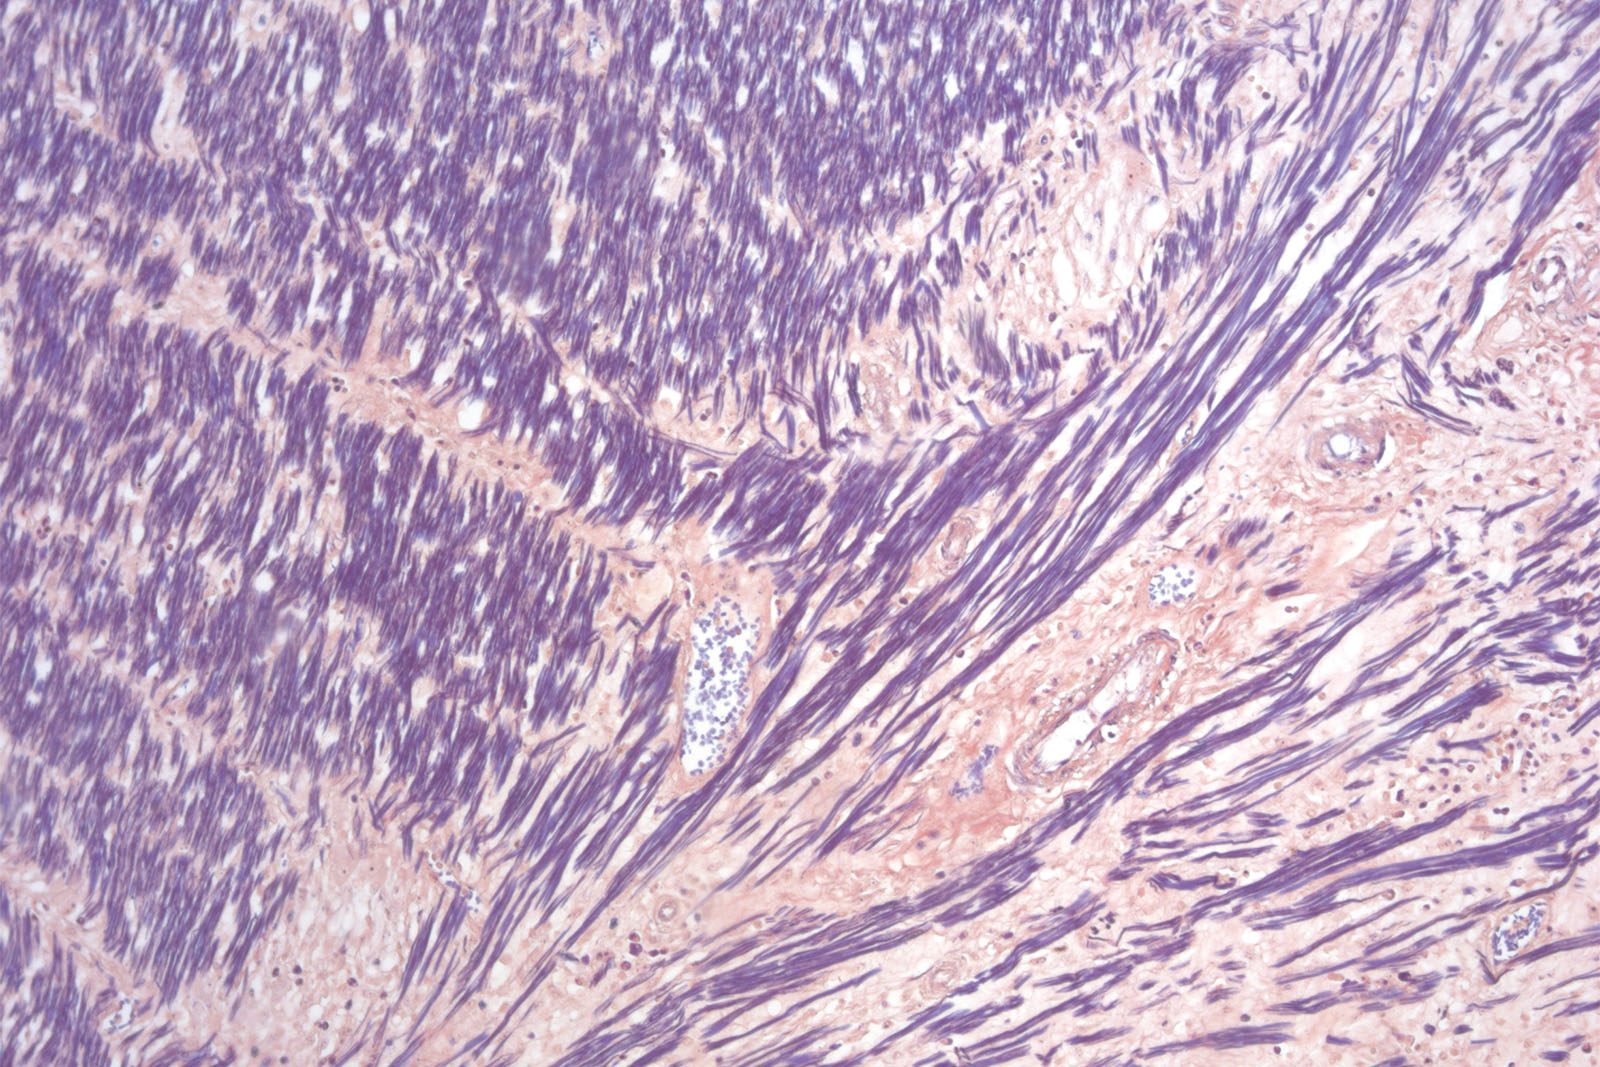

Hematoxylin P.T.A. kit is used for better visualization of elements of the central nervous system, fibrins, but primarily for differentiation between smooth and striated muscle tissue.

Four-reagent Hematoxylin-Phosphotungstic Acid kit for differentiation of smooth and striated muscle tissues as well as for the detection of fibrin, collagen and elements of the central nervous system according to Mallory.